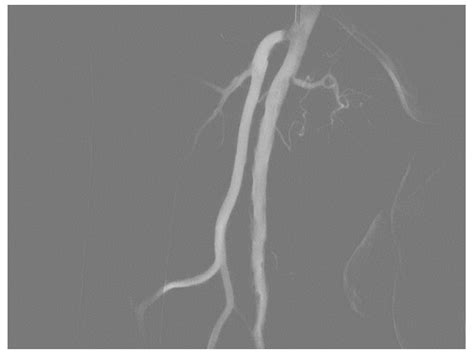

• Peripheral Vascular Disease: Assists in identifying blockages in the legs or abdomen that may require angioplasty or stent placement.

The landscape of Digital Subtraction Angiography continues to evolve with the integration of artificial intelligence and 3D reconstruction technologies. New systems are now capable of overlaying high-resolution DSA images onto live fluoroscopy, acting almost like a "GPS" for the surgeon. This 3D road-mapping technology reduces the amount of contrast dye required and improves the accuracy of placing complex endovascular devices.

As interventional techniques become more sophisticated, the role of high-fidelity imaging remains the cornerstone of modern vascular medicine. The transition toward hybrid operating rooms, where advanced DSA equipment is integrated directly into the surgical theater, further demonstrates the vital importance of this technology in saving lives and improving surgical outcomes.